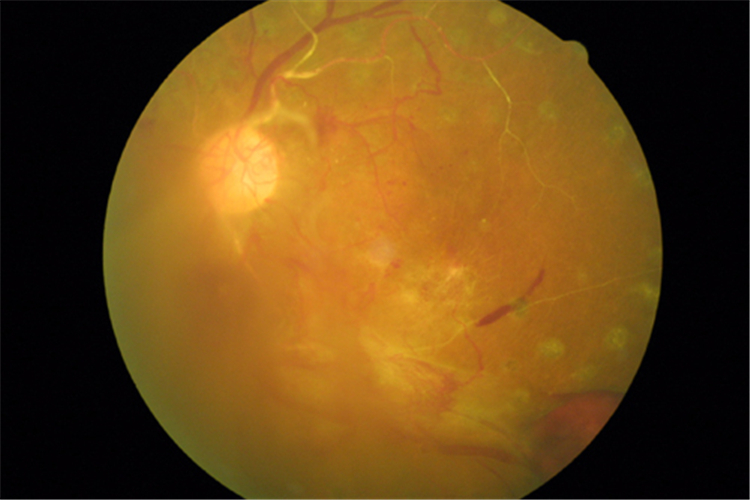

眼底視網膜脫落

眼底疾病使視網膜脫落

糖尿病人視網膜脫落